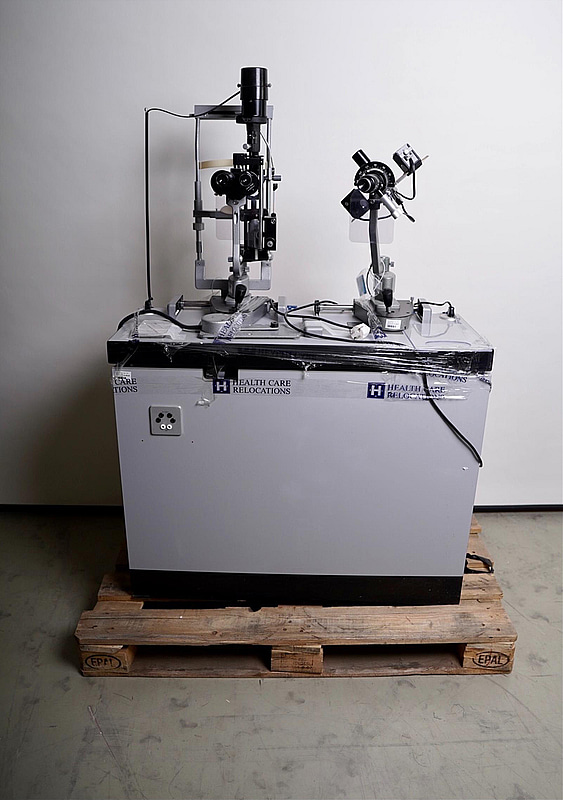

Optiker utrustning, undersökningsbord. Spaltlampa Haag-Streit 900.

Utlämning i Bromma efter ök.

Tjörn och BrommaFrakt